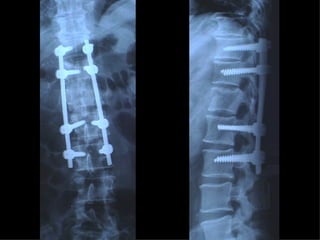

Fratture della colonna vetebrale

Tc pre op

frattura

TC RMN

Rx post

Timing chirurgico 1° GIORNO :- intervento salvavita - “Damage control” - trattamento chirurgico  primario differito 2°-3° GIORNO :  soltanto un “second  look”

5°-10° GIORNO :  “window of  opportunity”  per un intervento  definitivo 10°- 20° GIORNO : NESSUN TRATTAMENTO CHIRURGICO Dal 21° GIORNO : intervento chirurgico secondario - ricostruttivo